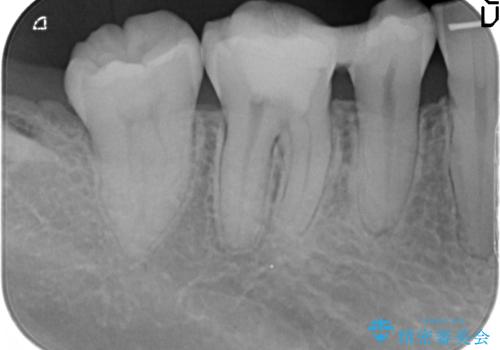

- 治療途中で数ヶ月放置してしまった歯のセラミック治療を希望され来院されました。

セラミッククラウン・セラミックインレーを用いた精密治療を計画します。